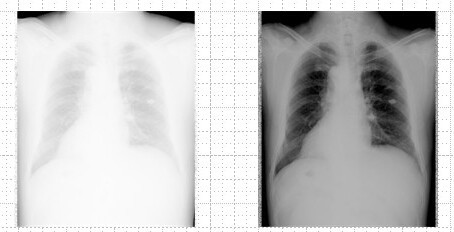

凌晨三点的CT室,李医生第17次滑动鼠标——屏幕中肺部磨玻璃影的边界随窗宽值,从模糊到清晰仅差30HU(亨氏)。这种决定诊断运的灰度调节艺术,正是医学影像的基石:窗宽窗位技术(Window Width & Level, WW/WL)24。

1980,需记忆百种组织参数:脑组织窗宽80-100HU、窗位35HU;骨骼窗宽2000HU、窗位400HU4。一次手动误差,或让细微骨折隐匿于过宽的灰度中。

🔍 搜索热词:AI窗宽技术 | 自适应窗宽 | CT值优化 | 医学影像灰度控制 | DICOM窗位算技术本质:窗宽控制CT值显示范围(如400HU),窗位设定中心值(如60HU),将人体组织-1000~3000HU的物理特性,压缩至显示器256级灰阶中6。每1%的调节偏差,可能意味着肿瘤边界的误判。